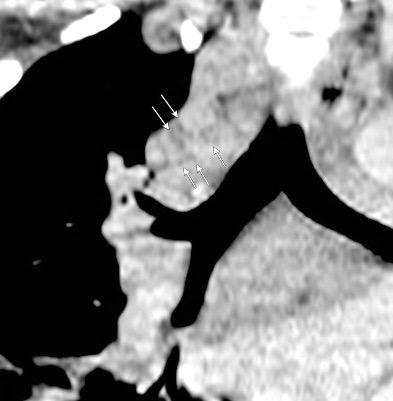

Anillo radiopaco formado por ganglios aumentados. El centro radiotransparente lo constituyen tráquea y bronquios centrales. Más frecuente en Tb y linfoma

Chiarenza et al. Chest imaging using signs, symbols, and naturalistic images: a practical guide for radiologists and non-radiologists. Insights into Imaging. 2019.